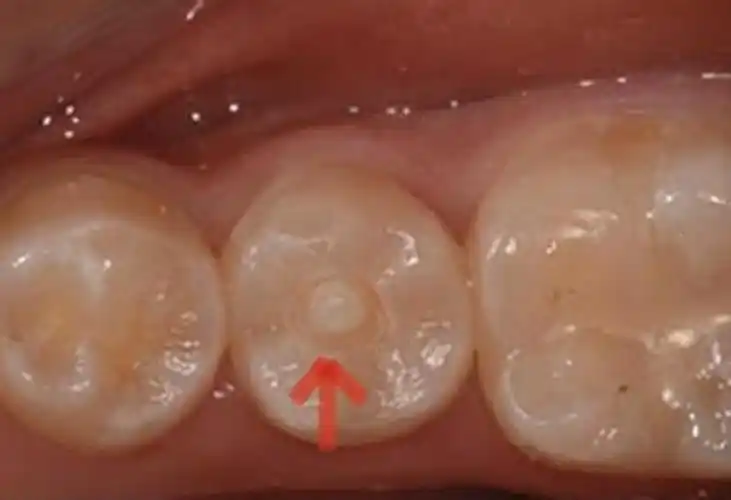

发生剧痛的这颗新萌出的恒牙,和其他牙齿相比,它中间多长了一个牙尖.

牙齿上的不定时炸弹畸形中央尖

畸形中央尖引起根尖周炎1例